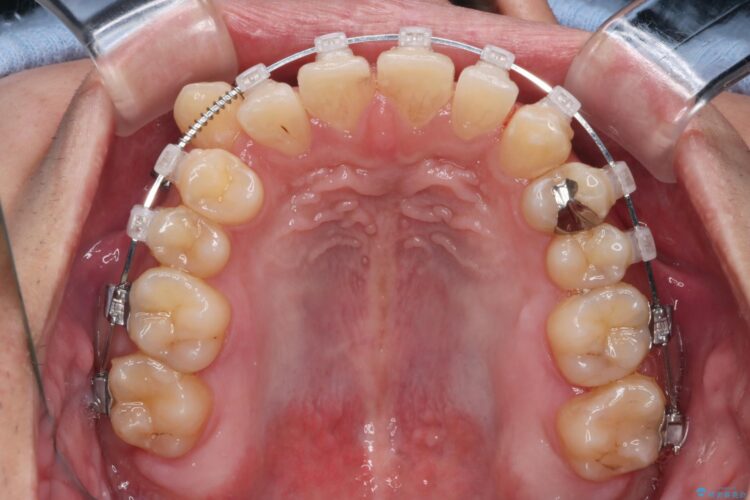

精密検査の結果、抜歯の必要はないと判断しました。臼歯を遠心移動させ、歯列をワイヤーで整えることでスペースを確保し、IPR(歯と歯の間を削る処置)を加えて歯並びを綺麗にする治療計画を立てました。

歯の移動にオープンコイルとMI(歯肉に埋入するネジ)を用いました。

非抜歯での治療だったため、1年半以内という短い期間で矯正を終了することができました。主訴であった八重歯とがたつきが改善され、大変ご満足いただきました。